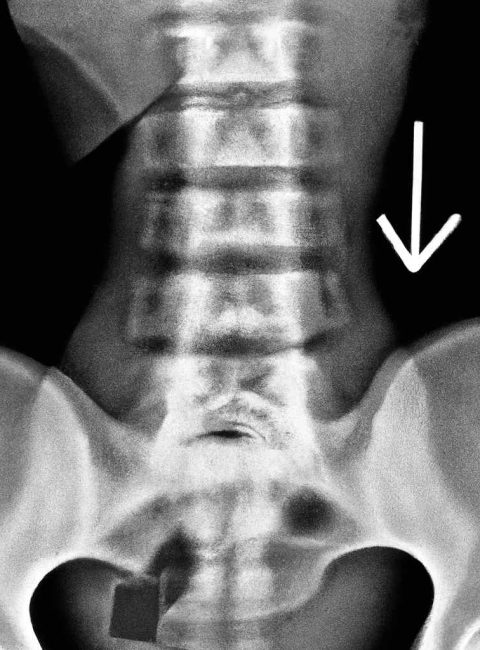

La diagnosi di una deviazione della colonna vertebrale inizia spesso con un esame fisico approfondito da parte di un medico specialista. Durante questo esame, il professionista valuta la postura del paziente e può richiedere radiografie per determinare l’entità della curvatura. In alcuni casi, potrebbero essere necessari ulteriori test, come la risonanza magnetica, per escludere altre condizioni sottostanti. La diagnosi accurata è essenziale per sviluppare un piano di trattamento efficace che sia su misura per le esigenze individuali del paziente.